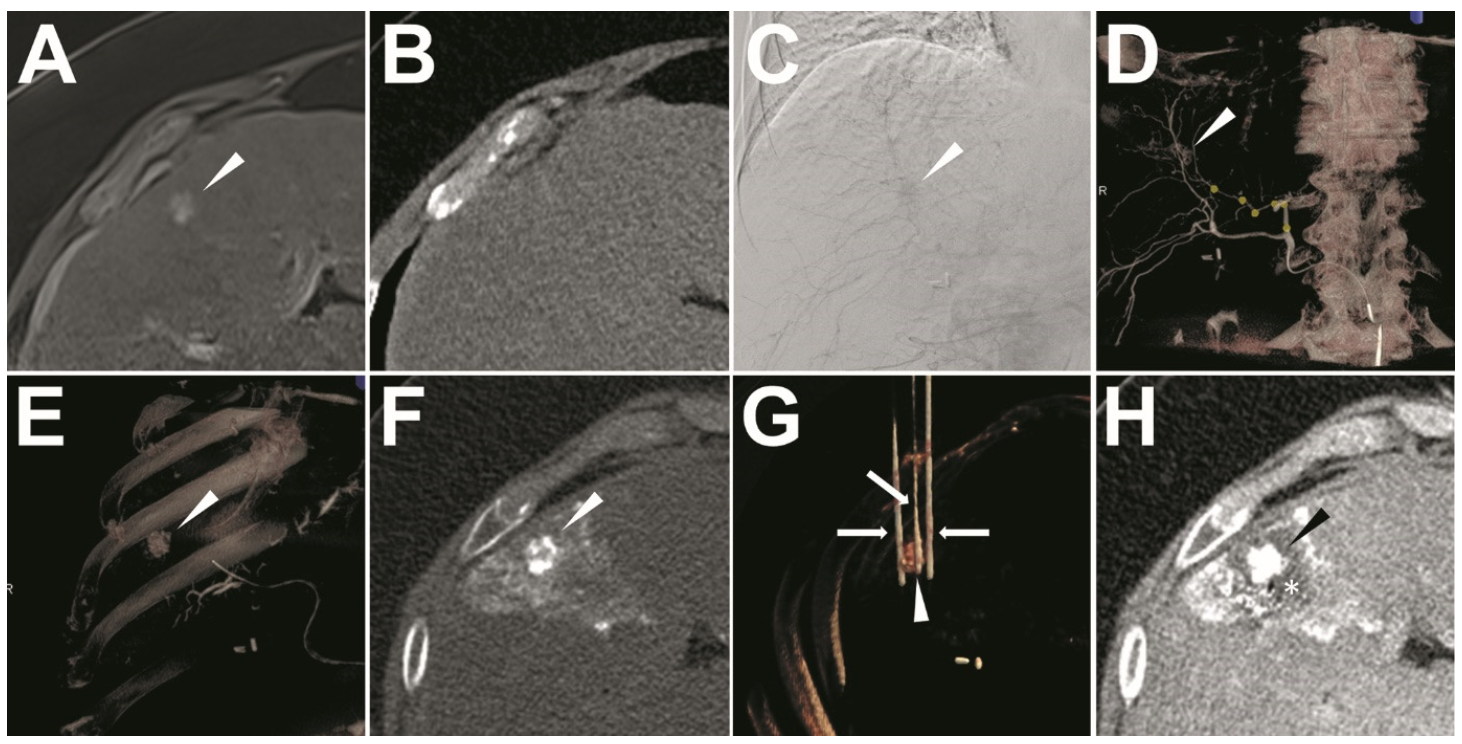

2.3. Ethiodized Oil Tumor Marking Procedure

2.4. IRE Treatment

3.2. Success of Ethiodized Oil Tumor Marking

3.3. Quantitative Analysis of the Visualization of Target-HCCs